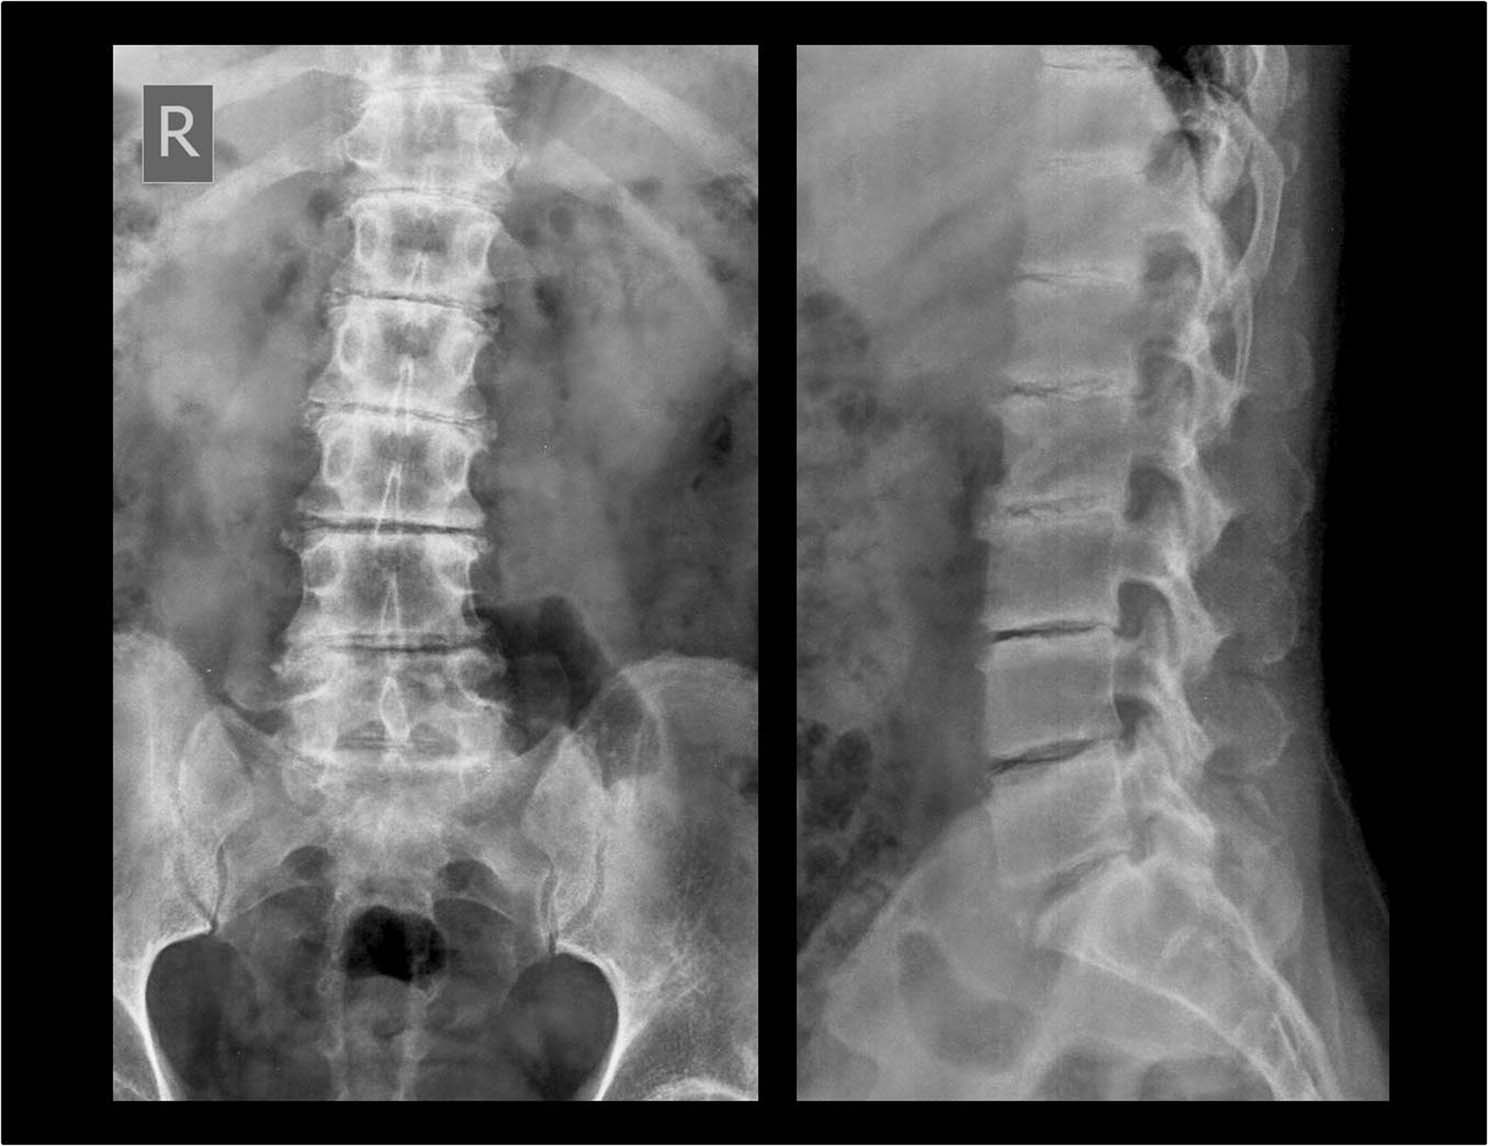

Damn good lifting advice. That’s a serious procedure, stay careful Man. At least you got to see your own insides on those X-rays though. That’s pretty cool. Keep that skeleton in check